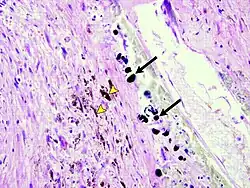

Gandy–Gamna nodules or Gandy-Gamna bodies, sometimes known as Gamna-Gandy bodies or Gamna-Gandy nodules, are small yellow-brown, brown, or rust-colored foci found in the spleen in patients with splenomegaly due to portal hypertension,[1] as well as sickle cell disease. They consist of fibrous tissue with haemosiderin and calcium deposits, and probably form due to scarring at sites of small perivascular haemorrhages.[2] They are visible on MRI scanning due to the presence of haemosiderin.[3]

Prolonged portal hypertention sometimes leads to the formation of Gamna-Gandy nodules.